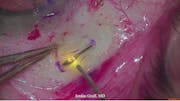

Susvimo: Surgical Pearls & Tricks #4 (Conjunctival closure)